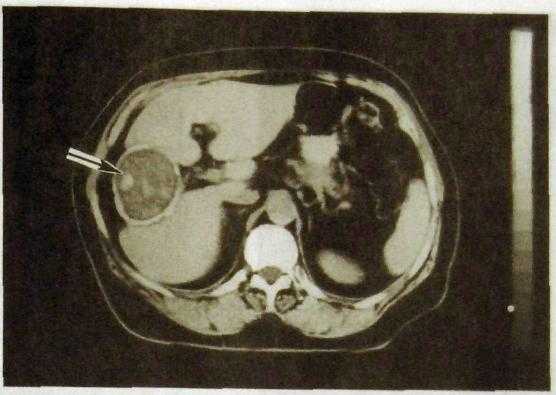

Рис. III. 138. Компьютерная томограмма печени. Эхинококковая киста с отложением извести в фиброзной капсуле кисты (указана стрелкой).

кольцевидные обызвествления наиболее характерны для эхонококковых кист. Одной из разновидностей кистозного поражения печени является поликистоз, при котором большая часть паренхимы органа замещена содержащими жидкость полостями. При этом заболевании кисты могут быть также в почках и поджелудочной железе.

На компьютерных и магнитно-резонансных томограммах киста отражается как округлое образование с ровными контурами, содержащее жидкость (рис. III. 138). Особенно хорошо видны кисты на усиленных компьютерных томограммах, т.е. полученных после введения контрастных веществ. Пространственное разрешение КТ и МРТ намного выше, чем со-нографии. При этих исследованиях удается выявить кистозные образования диаметром всего 2—3 мм. Сцинтиграфию печени редко применяют для выявления кист в связи с ее низким пространственным разрешением.